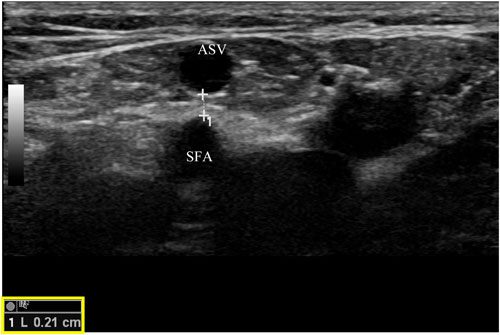

Một lưu ý khác là ở một số bệnh nhân có ASV giãn, tĩnh mạch có thể nằm rất gần với động mạch đùi nông (SFA), ngay tại hoặc xa bẹn (hình 5). Khi sử dụng kĩ thuật can thiệp nhiệt, cần phải đảm bảo khoảng cách an toàn giữa ASV và SFA, cũng như bơm một lượng thuốc tê đủ nhiều để tách hai mạch này ra xa nhau. Biến chứng thông động tĩnh mạch (AVF) đã được báo cáo trong một tình huống như thế này.